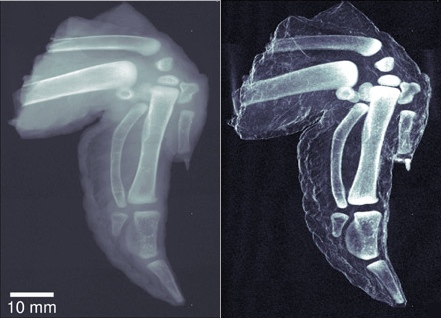

Egy új fejlesztésnek köszönhetően az ellenőrzési pontokon történő szűrések alkalmával a magas kontrasztú röntgensugarak révén már elkülöníthető a csont a szövettől, de akár a bomba a sajttól. A hagyományos röntgengépek ugyanis nem mindig tudják megmondani, hogy mit is „látnak” igazán, amikor az elektronok befékeződnek. Például egy tábla Tibi csokoládé mgkülönböztethetetlen bizonyos robbanóanyagoktól a hagyományos repülőtereken található csomagellenőrző futószalagok mellett működő röntgengépek számára. Így akár bárki átsétálhat egy jól álcázott bombával.

E célból (és természetesen orvosi alkalmazásának tökéletesítése érdekében is) néhány svájci tudós kifejlesztett egy magas kontrasztú röntgent, mely képalkotó technikája nem sokban különbözik a hagyományos mikroszkópokétól. Az eredmény: tökéletes kép, amelyen az erős kontraszt révén láthatóvá válnak a csonton található apró repedések is. A rendszer meglehetősen drága, de megéri alkalmazni a biztonságunk érdekében, így nyugodtan repüljünk Svájcba csokoládéért, vagy Franciaországba sajtért, és a teli csomagjainkkal zavartalanul átrepülhetünk az USA-ba különösebb fennakadás nélkül.